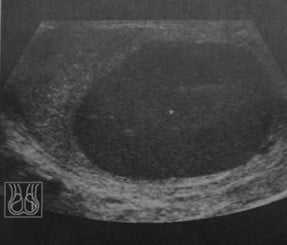

Что покажет УЗИ нормальной мошонки

- орган овальной формы

- размеры: 4-5х2-Зх2-2,5 см

- объем: 15-20 мл

- умеренная эхогенность и четкая гранулярная акустическая структура

- размером 1,5 х 1 см, пониженной эхогенности

- содержащееся небольшое количество серозной жидкости не следует путать с гидроцеле.

- тонкая эхогенная линия вокруг яичка

- лучше всего видна в зоне средостения яичка.

Нормальный верхний полюс яичка. Картина при продольном УЗ-сканировании. Более высокая эхогенность яичка в области полюса по сравнению с расположенной рядом головкой придатка яичка (заполненная стрелка). Небольшое количество жидкости в мошонке (открытая стрелка) является нормой.